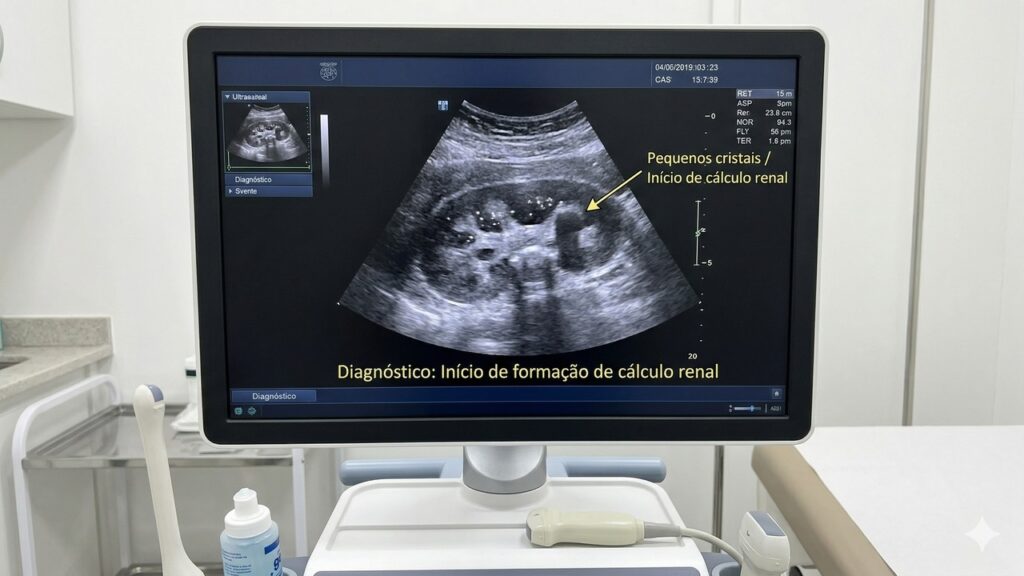

Ultrassom mostra pequenos cristais no rim indicando formação inicial de pedra nos rins.